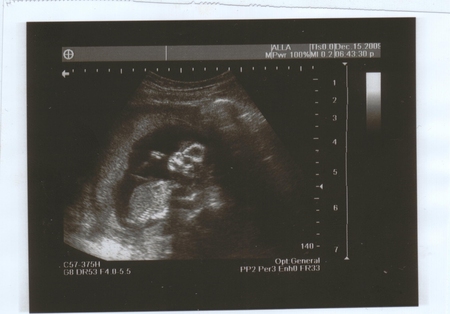

Даже в сегодняшнем гороскопе на ББ написано, что у меня целый день будет блаженное настроение до самого вечера! Ладно, ближе к теме)))) Кароче, пришла я на УЗИ, живот намазали, и тетя-врач в монитор смотрит и говорит, что малыш большой, здоровый, всё на месте, на неделю больше своего срока, то есть, срок по месячным у меня 14 недель и 4 дня, а по УЗИ 15 недель и 4 дня!))) о как!!! Богатырь или богатырша!!!! Переднее предлежание плаценты.. или чего-то там... КТР - 95 мм.Сказала, что у меня все отлично, ни тонуса, ни чего-то ещё.. все в порядке))) Потом повернула монитор и я увидела своего малыша. Она мне ласково начала рассказывать, где ножки, ручки.. да я и сама все видела!!!! Это на фотках плохо видно, а в живую, когда он шевелится - отлично. Я видела всё!!! Он мне и махал и палец сосал!))) Действительно, было состояние блаженства. Я только охала и ахала, просто удивлялась.. не ужели.. этот живой малыш у меня в животе?!)))) Вот и малыш и вопрос, что на 3-й фотографии??? Мы с мужем не поняли))) кто знает, напишите, пожалуйста!)))

здорово! на третьей фотке похоже головка сверху и там разметки такие это размер головки меряли)) я тоже делала узи, на 17 недели, мне тоже ставили на неделю больше срока, и сказали что похоже на девочку)) фото получилось очень отчетливое, смотрю и любуюсь)) так приятно...